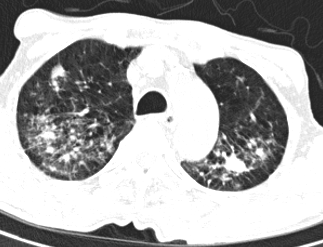

Hay trường hợp người bệnh D.V (79 tuổi) ở Tam Nông, Phú Thọ, chỉ đi kiểm tra sức khỏe do đau bụng nhưng sau khi chụp kiểm tra phổi thì phát hiện tổn thương thâm nhiễm và xơ hoá cả hai phổi, xét nghiệm dịch phế quản có vi khuẩn lao.

| Hình ảnh phổi của người bệnh Đ.V đã bị thâm nhiễm, xơ hoá hai đỉnh phổi - Ảnh BVCC |